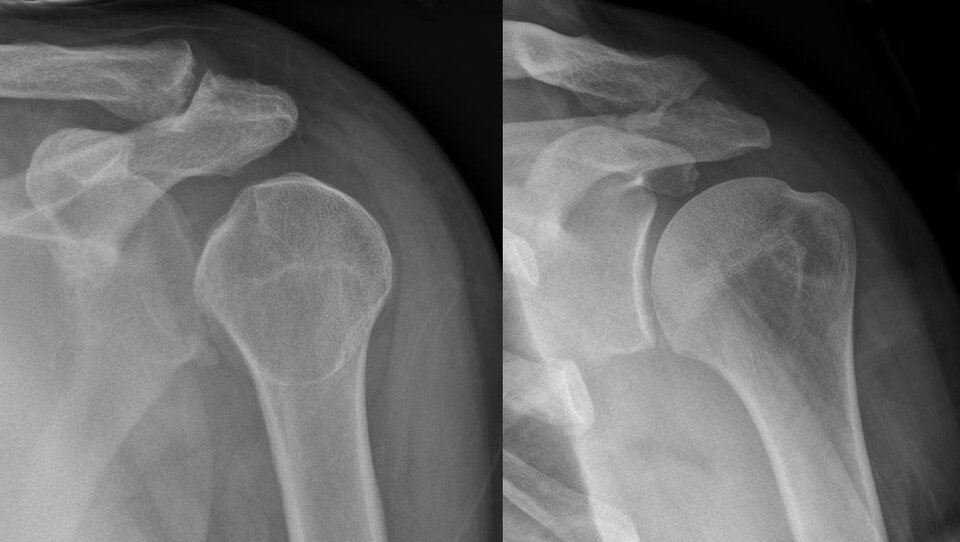

Na podstawie fotografii wyjaśnij, na czym polega zwichnięcie stawu. (Uzupełnij).

Zdjęcie rentgenowskie: zwichnięty staw barkowy (po lewej) oraz zdrowy (po prawej).

W przedstawionym zwichnięciu stawu barkowego doszło do przemieszczenia głowy kości ramiennej względem względem łopatki.